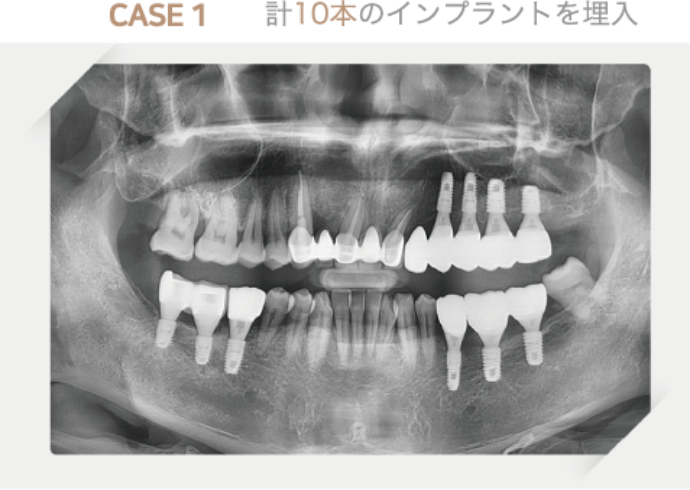

オールオン4・オールオン6

オールオン6は、歯を失ってしまった方にとって、非常に魅力的な治療法の一つです。上顎または下顎の歯のすべてを、たった6本のインプラントで支える治療法で、短期間で固定式の入れ歯を装着できることが大きな特徴です。

ただし、デメリットや適正条件を知っておくことも治療を行う上では欠かせません。当クリニックでは、患者様のお口の状態やお考えに合わせた治療法をご提案させていただきます。